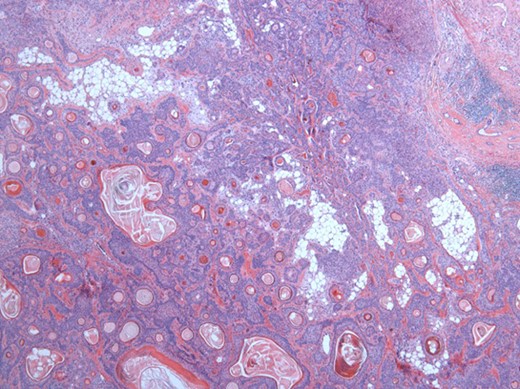

The surgical specimen showed a well-delineated submucosal nodule of 1.7 cm in the greatest diameter, without ulceration. Microscopically, this lesion appeared well defined with a central canal lined by keratinizing squamous epithelium without atypia (Fig. 2). In addition, we found confluent squamous foci with keratinizing centers (Fig. 3). The stroma was mostly fibrous, with occasional adipose and myxoid tissue. Only in the periphery of the lesion did we see a thin layer of normal ductal structures, highlighted by epithelial membrane antigen (EMA) positivity of the luminal cells, with immunochemistry studies (Fig. 4), whereas the other cellular component consisted of myoepithelial cells, highlighted by smooth muscle actin (SMA) and S100 protein (Fig. 5). No mucous secreting cell could be found. Keratin 5/6 and 903 were all positive for the whole specimen. The above-mentioned histopathologic findings helped to conclude the diagnosis of a PA with extensive squamous metaplasia. Margins were negative.

Well-circumscribed tumor on low power view. Hematoxylin and eosin (H&E ×25).